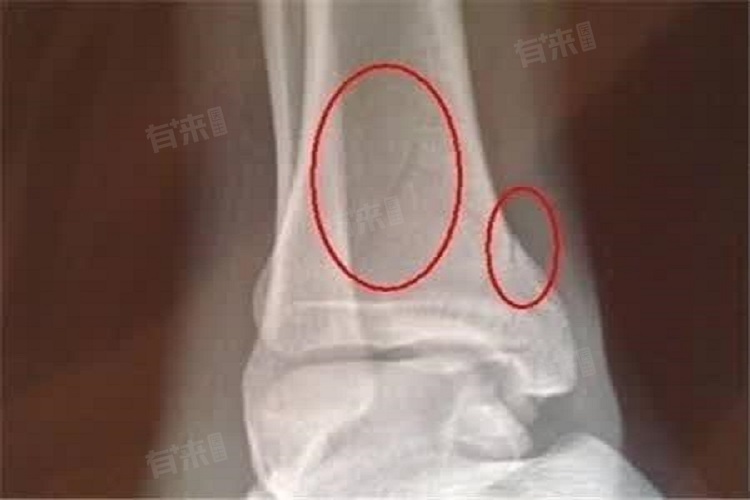

骨折后长骨痂时,身体会出现一系列反应,主要体现在疼痛、局部感觉及肢体功能等方面,是骨折愈合进程的外在表现,能帮助患者和医生了解骨折恢复情况。

1、疼痛减轻:骨折初期,断裂处疼痛剧烈,随着骨痂开始生长,骨折断端逐渐被连接、固定。骨痂的形成意味着骨折部位开始修复,对周围神经的刺激减少,疼痛随之减轻。从最初难以忍受的剧痛,转变为程度较轻的隐痛,且疼痛发作频率降低,是骨折长骨痂的常见反应,也是骨折愈合的积极信号。

2、局部肿胀消退:骨折发生后,受伤部位会因出血、炎症反应出现肿胀。在骨痂生长阶段,骨折处的血管开始重建,血液循环逐渐恢复正常。身体吸收淤血,炎症消退,局部肿胀随之慢慢消退。原本肿胀明显、皮肤紧绷的部位,逐渐恢复正常形态,皮肤的紧绷感减轻,这也表明骨折愈合在有序进行。